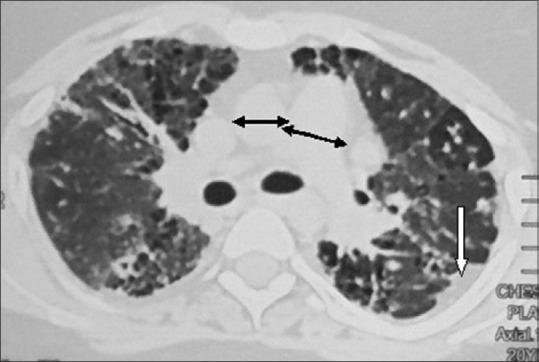

Chronic HP from exposure to avian antigen was diagnosed when the high resolution computerized tomography (HRCT) showed features for HP and was supported by the history of exposure to pigeons, the presence of precipitin antibodies (IgG) to avian antigen in high titre with negative rheumatoid factor, antinuclear antibody, and no clinical clue for a collagen vascular disease. The HRCT changes were noted on Likert scale (0-5) in terms of affection of peripheral and/or axial involvement, reticulation, honeycombing, haze, mosaic, traction bronchiectasis, pleural reactions, features of pulmonary hypertension, and air cysts. Cardiomegaly and independent cardiac chamber enlargement were also recorded.

The lower lobes were predominantly (65.6%) affected with similar frequency (78.1) of peripheral and axial parenchymal affection. The parenchymal changes in HRCT were haze or ground-glass opacity (100%), mosaic appearance (93.75%), reticulations (68.75%), traction bronchiectasis (34.3%), air cysts (21.8%), and honeycombing (9.37%). Pleural reactions, though not described so far, were found in 50% of cases. Features of pulmonary hypertension (87.5%), cardiomegaly (50%), left and right atrial enlargement (81.2% and 78.1%), and right ventricular enlargement (31.2%) were the common echocardiography findings.

Chronic HP from avian exposure shows predominantly lower lobe involvement with haze, reticulation, features of pulmonary hypertension, and pleural reactions as common HRCT findings. The likelihood of pulmonary hypertension appears high and although honeycombing is often present, the classical UIP pattern has not been found.